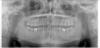

asl028 Опубликовано 27 марта, 2008 Поделиться Опубликовано 27 марта, 2008 Здравствуйте. В одной из клиник мне сделали ортопантомограмму и обнаружили кисты на нижних 6-х. В 2001 году в этих зубах были удалины нервы, прочищены каналы, установлены штифты и запломбированы. С тех пор они меня не беспокоят.В этой клинике лечением кисты не занимаются и предложили удалить оба зуба, но я пока отказался. Хочу проконсультироваться у других врачей о возможности лечени кисты с сохранением зубов. Взгляните пожалуйста на снимок. Можно ли что-нибудь порекомендовать в моем случае? P.S. Снимок в формате JPEG, но могу выложить и оригинал в формате TIF (2Mb). Заранее спасибо.Сергей.С.-Петербург. Ссылка на комментарий

Андрей Опубликовано 27 марта, 2008 Поделиться Опубликовано 27 марта, 2008 Здравствуйте. В одной из клиник мне сделали ортопантомограмму и обнаружили кисты на нижних 6-х. В 2001 году в этих зубах были удалины нервы, прочищены каналы, установлены штифты и запломбированы. С тех пор они меня не беспокоят.В этой клинике лечением кисты не занимаются и предложили удалить оба зуба, но я пока отказался. Хочу проконсультироваться у других врачей о возможности лечени кисты с сохранением зубов. Взгляните пожалуйста на снимок. Можно ли что-нибудь порекомендовать в моем случае? P.S. Снимок в формате JPEG, но могу выложить и оригинал в формате TIF (2Mb). Заранее спасибо.Сергей.С.-Петербург.Только по снимку судить тяжело. Мне кажется, что на левой шестерке у Вас между корней разряжение. Это может осложнить лечение. В остальном согласен с Др.Гео. Ссылка на комментарий